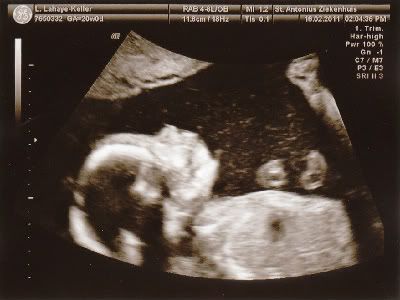

Lijkt me duidelijk wat het wordt hahahahaha.....!!!

Voor degene die niet zo goed in echo's zijn......

We gaan straks beschuit met blauwe muisjes smeren!